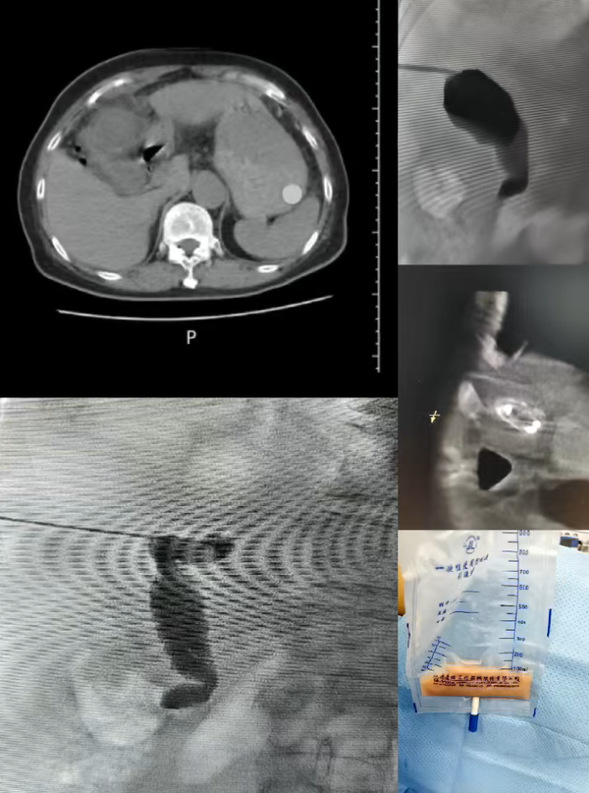

大年初一,一名化脓性胆囊炎患者被紧急送入医院。患者因严重炎症持续高烧不退,体温一度升至39.5℃以上,经保守治疗后症状无明显缓解,病情持续进展。我院介入科主任莫庆国团队接诊后迅速评估,考虑到患者感染较重,保守治疗难以控制,决定急诊实施经皮肝穿刺胆囊引流术。手术穿刺精准,引流顺利。术后,患者高烧消退,腹痛症状明显缓解,家属悬着的心终于放下。

介入科团队为化脓性胆囊炎折叠胆囊并胆管集气患者进行急诊胆囊穿刺引流

我院介入科主任莫庆国团队手术画面